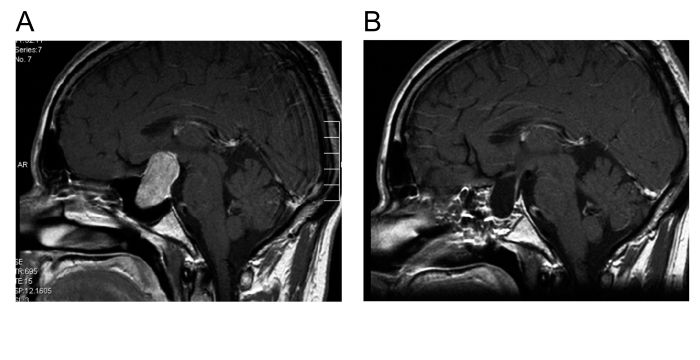

Links(A): Kernspintomographie eines großen intrasellären und suprasellären Hypophysenadenoms. Rechts(B): Die postoperative Kernspintomographie bestätigt die vollständige Entfernung des Hypophysenadenoms.

Links: Kernspintomographie eines großen intrasellären und suprasellären Hypophysenadenoms. Rechts: Die postoperative Kernspintomographie bestätigt die vollständige Entfernung des Hypophysenadenoms.